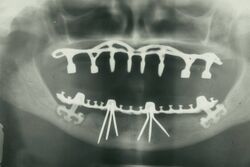

The modern movement of evidence-based dentistry calls for the use of high-quality scientific research and evidence to guide decision-making such as in manual tooth conservation, use of fluoride water treatment and fluoride toothpaste, dealing with oral diseases such as tooth decay and periodontitis, as well as systematic diseases such as osteoporosis, diabetes, celiac disease, cancer, and HIV/AIDS which could also affect the oral cavity. Other practices relevant to evidence-based dentistry include radiology of the mouth to inspect teeth deformity or oral malaises, haematology (study of blood) to avoid bleeding complications during dental surgery, cardiology (due to various severe complications arising from dental surgery with patients with heart disease), etc.

By nature of their general training, dentists, without specialization can carry out the majority of dental treatments such as restorative (fillings, crowns, bridges), prosthetic (dentures), endodontic (root canal) therapy, periodontal (gum) therapy, and extraction of teeth, as well as performing examinations, radiographs (x-rays), and diagnosis. Dentists can also prescribe medications used in the field such as antibiotics, sedatives, and any other drugs used in patient management. Depending on their licensing boards, general dentists may be required to complete additional training to perform sedation, dental implants, etc.